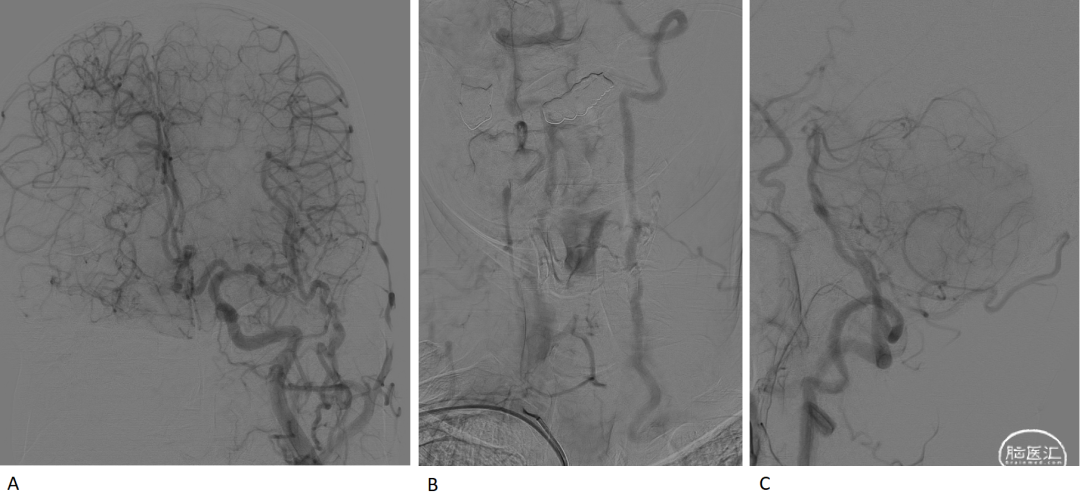

A.DSA示右侧颈内动脉起始段闭塞,头端圆钝(图A红圈),提示慢性闭塞可能,右侧颈外动脉通过眼动脉代偿代偿右侧大脑中动脉供血区。

A.前交通开放,左侧颈内动脉通过前交通代偿右侧大脑前动脉,右侧大脑前动脉通过脑膜支代偿右侧大脑中动脉供血区,B-C.左侧锁骨下动脉起始段闭塞并盗血。

右侧椎动脉造影示基底动脉尖闭塞,如红圈所示,双侧大脑后动脉未见显影。